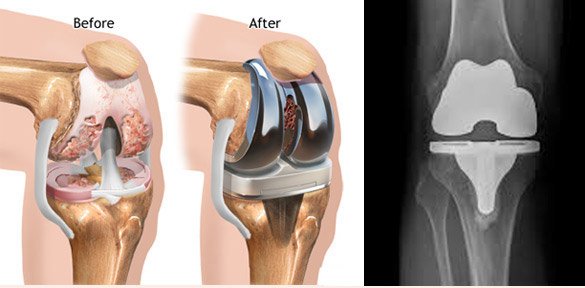

In knee replacement surgery, the bone surfaces and cartilage that have been damaged by arthritis are shaved off and replaced with artificial surfaces made of metal and a plastic material. We call these artificial surfaces “implants,” or “prosthesis.”

In total knee replacement or TKR a small amounts of the bone surface are removed from the front, side and back of the femur (thigh bone). This shapes the bone so the implants will fit properly. The amount of bone that is removed depends on the amount of bone that has been damaged by the arthritis.

A small portion of the top surface of the tibia(leg bone) is also removed, making the end of the bone flat.

The back surface of the patella (kneecap) is also removed.

An implant is attached to each of the three bones. These implants are designed in such a way that the knee joint will move in same fashion as that the original knee joint moved when it was healthy. The implants are attached using a special kind of cement for bones.

The implant that fits over the end of the femur is made of metal. Its surface is rounded and very smooth, covering the front and back of the bone as well as the end.